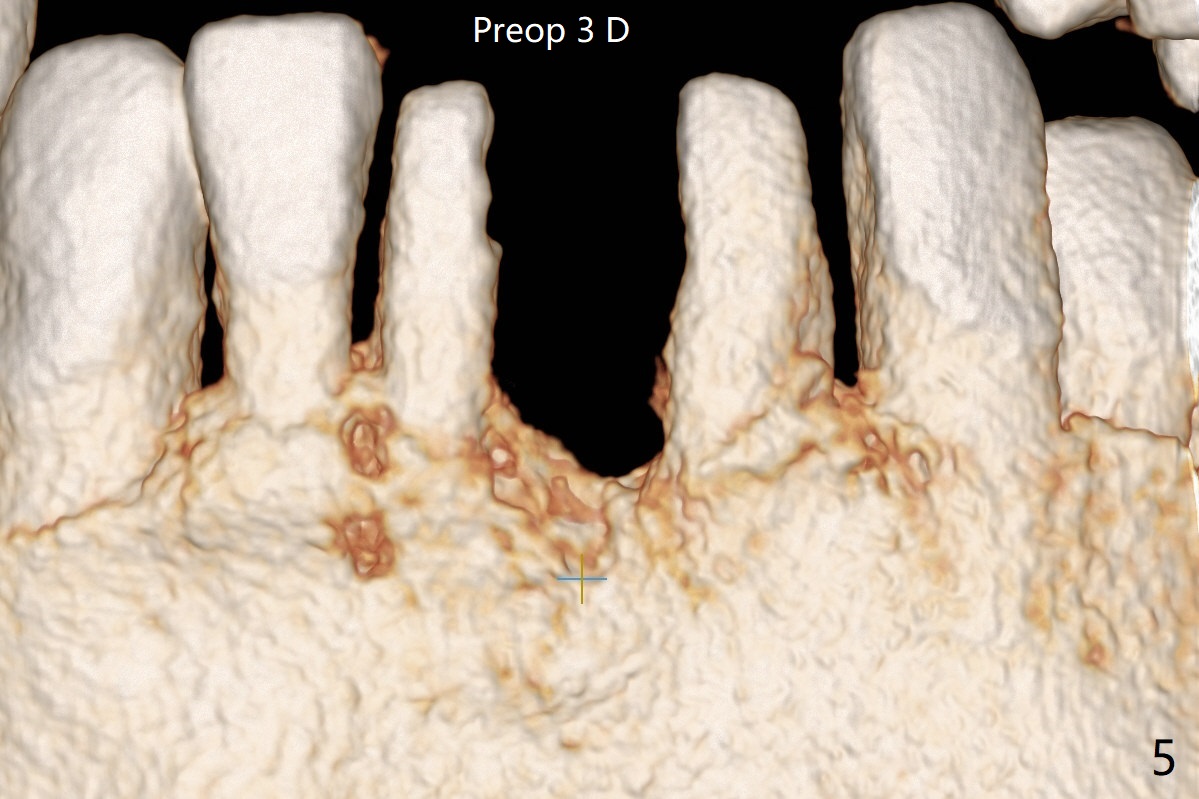

经过深洗以及改善口腔卫生,术前下前牙区牙龈基本没有红肿,但是缺牙处牙龈凹陷(图一,二:箭头),这个现象代表什么?如何影响手术进路?其实后者部分是因为牙龈与下面骨质(骨嵴)粘连(图三:*)产生的,分离粘骨膜瓣时不小心撕裂颊侧牙龈(图三(骨膜分离器下面:#),造成后来缝合困难,需要多用一个胎盘膜)。如果术前仔细分析CT 3D图像(图四,五)可以发现严重颊侧骨壁凹陷(图三:^)以及骨嵴(图四:*),事先抽血制备PRF膜和粘性骨粉,植骨效果好些(图六)。术中发现缺损,再抽血会拖延手术。最后将就用血调袢骨粉,使用胶原膜和胎盘膜覆盖(图七,八)。颊侧裂口术后十天愈合了(图九,十)。术后一个月颊侧牙龈凹陷,牙桥边缘(图十一:箭头)粗糙,临时牙桥取出,调整边缘,有利于局部卫生(图十二)。术后两个月桥边缘光滑(图十三:箭头),局部卫生和牙龈凹陷有所改善。病人将一个半月后回来取模。Return to Protect Graft 前磨牙即种 101 Xin Wei, DDS, PhD, MS 1st edition 04/30/2021, last revision 07/03/2021